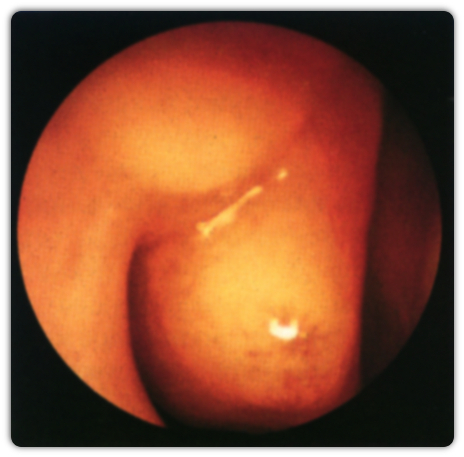

ΦΥΣΑΛΛΙΔΩΔΗΣ ΚΟΓΧΗ